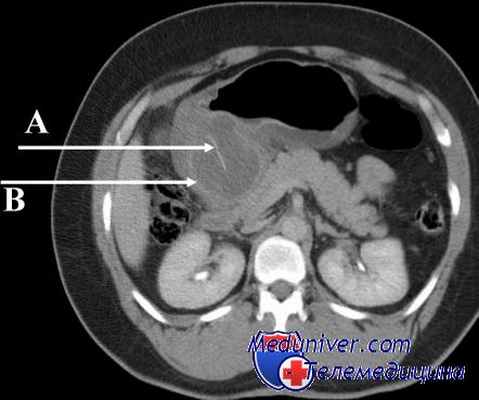

Синдром приводящей петли был у 3 больных. Диагноз подтвержден рентгенологически. Мы должны отметить, что кратковременное, малыми порциями попадание бария в приводящую кишку констатируется довольно часто, но клинически это ничем не проявляется, и ни о каком синдроме приводящей петли здесь говорить не приходится. У больных с синдромом приводящей петли в нее попадает много бария, он долго там задерживается, сама петля расширена. Клинически это проявляется чувством тяжести и распирания в эпигастрии после еды, рвотой желчью, после чего наступает облегчение. При тяжелых формах синдрома рекомендуется оперативное лечение, которое заключается в пересечении приводящей кишки и наложений анастомоза по Ру.